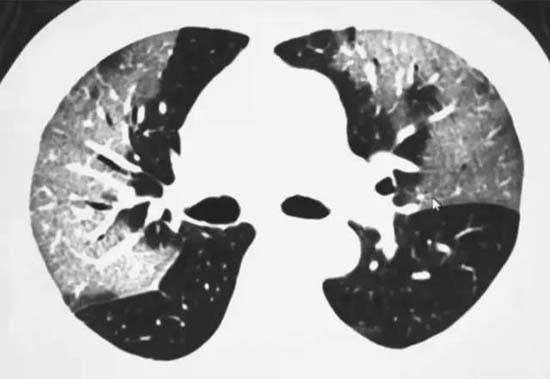

近日,武汉大学中南医院医学影像科副主任张笑春教授在朋友圈发布的“强烈推荐CT影像作为目前新冠肺炎首选诊断方法”言论,引起社会广泛关注。日前,国家卫生健康委办公厅和国家中医药管理局联合印发《新型冠状病毒感染的肺炎诊疗方案(试行第五版)》,将“疑似病例具有肺炎影像学特征者”作为湖北省临床诊断病例标准。

“病毒核酸检测是最终确诊新冠肺炎无创诊断的金标准,然而‘CT阳性、核酸阴性’的检测结果,可能影响临床排查。目前,新型冠状病毒核酸检测特异性高、敏感性偏低,不排除存在部分假阴性。”张笑春认为,新型冠状病毒被发现不久,检测和诊疗仍需要一定认识的过程,加上核酸试剂盒研发时间较短,现有采样人员紧缺等因素,短期内对大量患者检测排查存在一定困难。

“CT检查方便、快捷、直观,在基层医院易于普及。虽然CT只是辅助诊断手段,但在新冠肺炎形势严峻的今天,武汉等地的防控必须采取‘不放过一个’的非常规手段,减少交叉感染。”张笑春提醒,CT阳性和病毒核酸检测阴性的患者,也要被纳入隔离治疗范畴,非常时期“宁错勿漏”。只有这样才能尽快控制传染源、切断传播途径。

对此,国家医疗专家组成员、北京地坛医院感染性疾病诊疗与研究中心首席专家李兴旺明确回应:把CT检查结果作为诊断标准在我们几版诊疗方案中一直存在;救助方案一直强调,只要是疑似病例以上的病人,要及时送到定点医院。“当然影像学有典型的表现,包括其他表现,我们认为它是一个临床诊断病例,需要及时开展积极的救治。”

“但是,新冠肺炎有较为特别的影像特征。”王从颖介绍,在武汉当前的疫情下,试剂盒缺乏时,CT影像明确的情况下,结合流行病学史,可以作出初步判断。